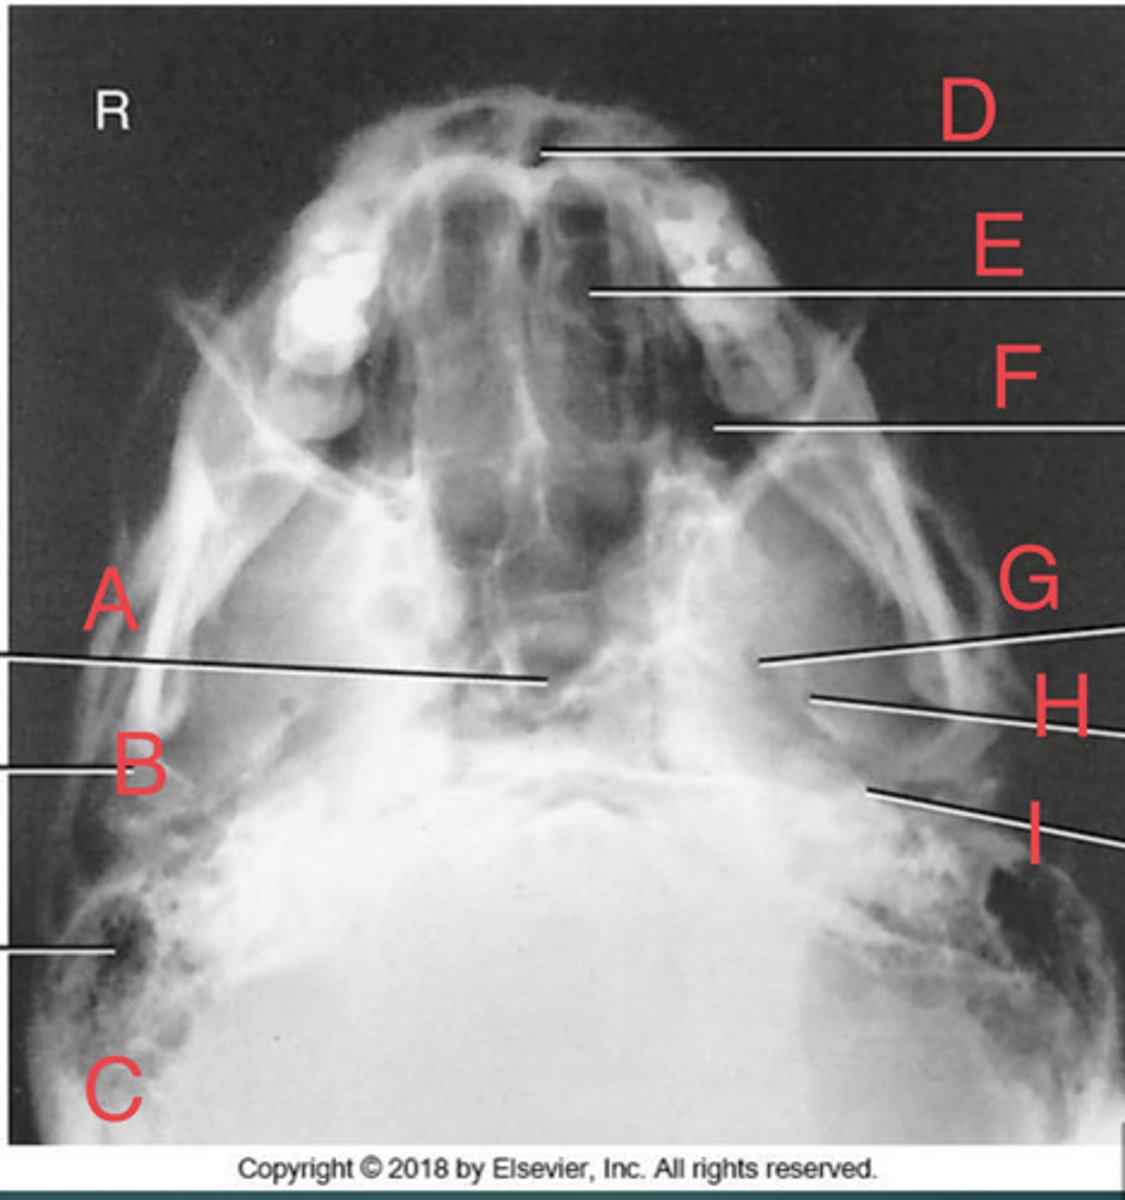

SMV sinuses

What position?

Sphenoid sinus of sphenoid bone

A.

R mandibular condyle of mandible

B.

R Mastoid air cells of temporal bone

C.

Nasal fossa

D.

L. Ethmoid sinus of ethmoid bone

E.

L maxillary sinus of maxilla

F.

L foramen ovale of sphenoid bone

G.

foramen spinosum of sphenoid bone

H.